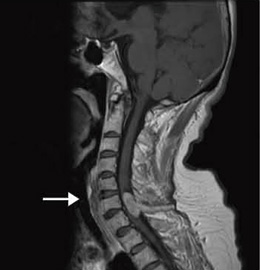

症例3:頸髄腫瘍

70歳,女性。4年ほど前から歩行障害が進行。下肢に強い四肢麻痺の状態があり,T1強調像にて第6,7頸椎間に造影増強される腫瘤を認めた。左第7頸神経から発生した神経鞘腫と診断した。

T1WI,FSE,TR/TE:450/12,FOV:250mm,スライス厚:4.0mm